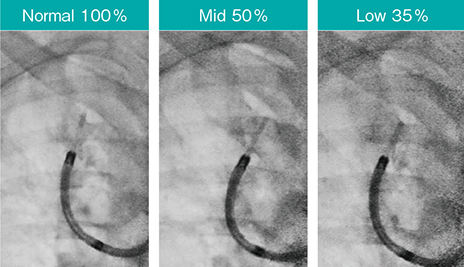

3.透視パルスレートと透視線量モード

Ultimax-iは、ダイヤルを回すだけで透視パルスレートを1.0~15fpsまで調整可能で、例えばoctave SPに加え透視パルスレートを7.5fpsに設定することで、従来よりも約82.5%の被ばく低減(従来の17.5%の線量)が実現する。さらに、透視線量モードをNormalモード(標準の線量)、Midモード(標準の50%の線量)、Lowモード(標準の35%の線量)の3段階から透視を切らずにワンタッチで選択できる(図10)。画質は大きく変わらないため、ルート確認後はNormalモードからMidモードにするなど、透視パルスレートと同様に細やかな使い分けが可能である(図11)。

図10 検査に応じた透視線量モードの切替はワンタッチ

図11 透視線量モードによる画質の比較

Accent適用、スコープ:BF-P290、ガイドシース:SG-400C(オリンパス社製)